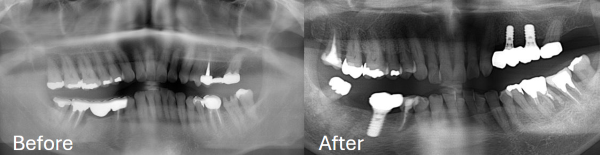

IMPLANT

専用オペ室で安全に行う インプラント治療

インプラント治療は、オペ専用の診療室で経験豊富な歯科医師が担当します。歯科用CTを用いた精密な診査・診断と治療を行います。また、口腔外バキュームでの衛生管理を徹底しています。